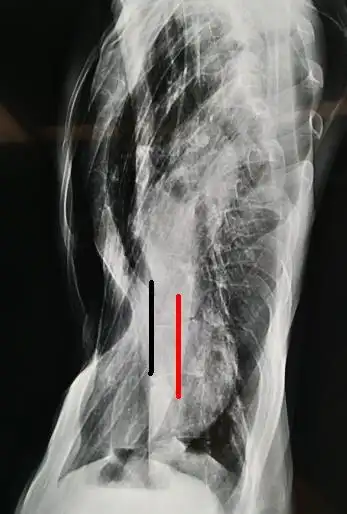

图4,脊柱侧弯,心脏位于左侧胸腔.